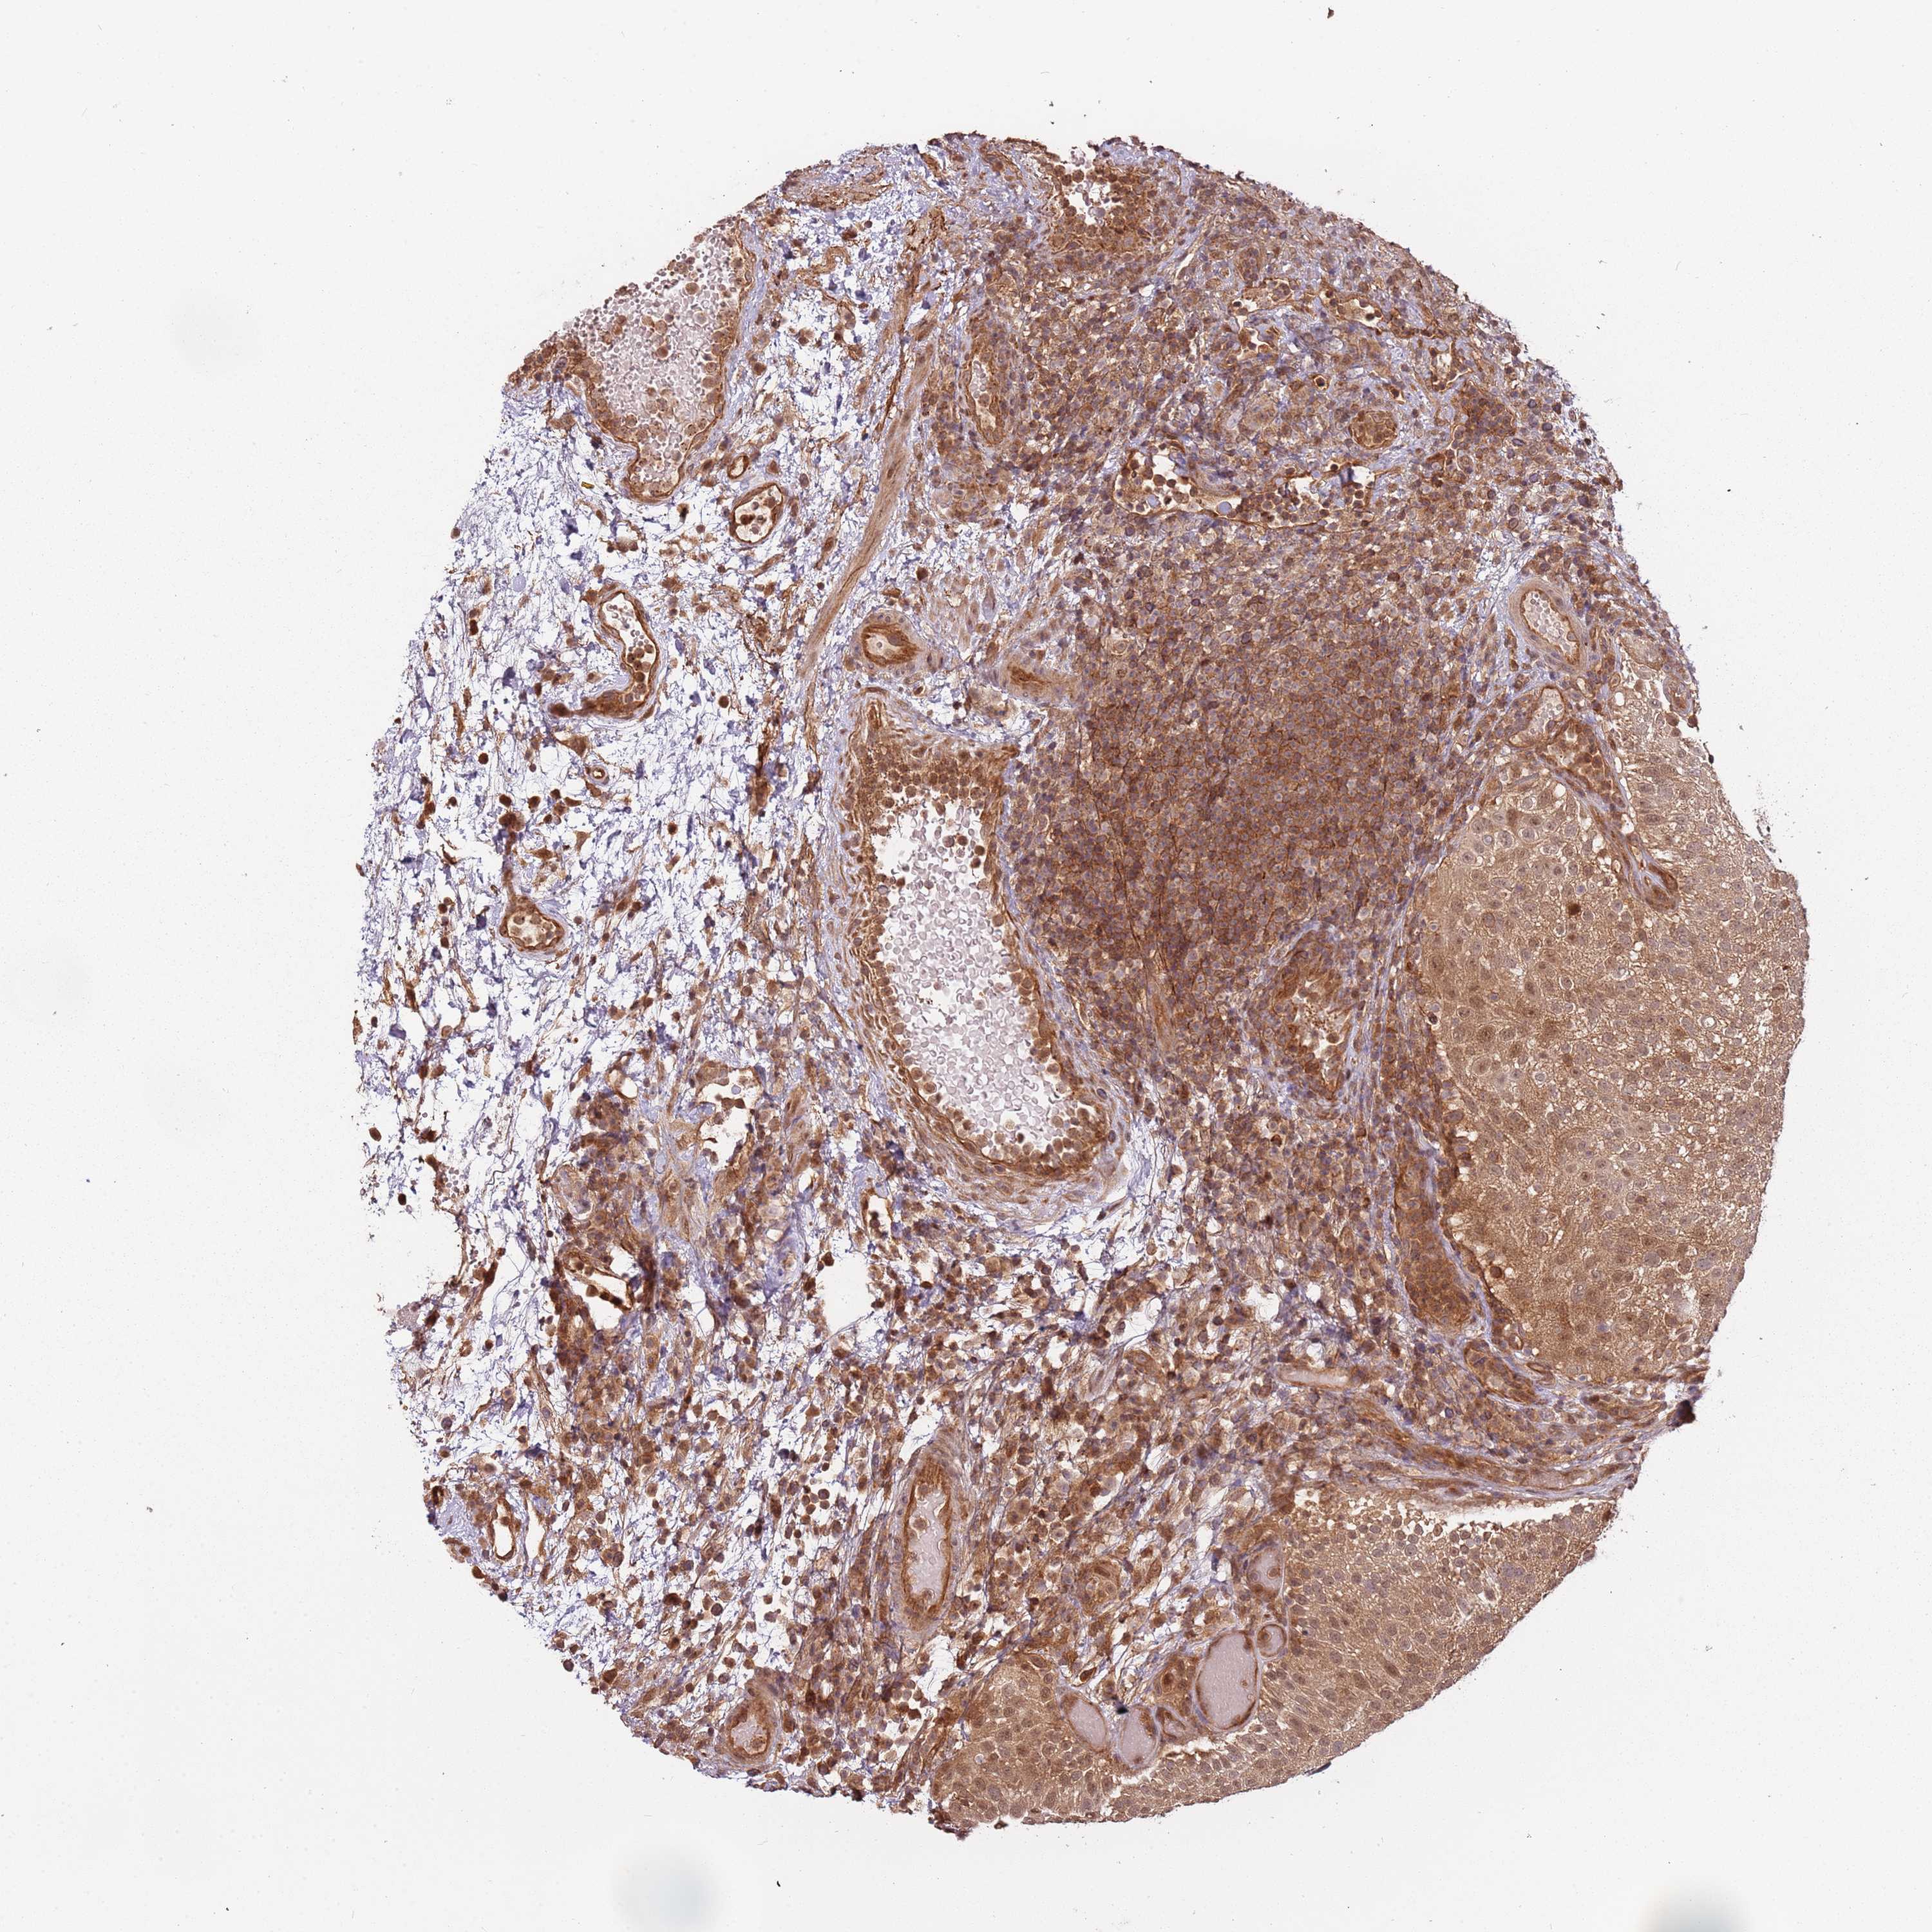

UROTHELIAL CANCER - Protein expressioni

A mouse-over function shows sample information and annotation data. Click on an image to view it in a full screen mode. Samples can be filtered based on level of antibody staining by selecting one or several of the following categories: high, medium, low and not detected. The assay and annotation is described here.

Antibody stainingi

Antibody staining in the annotated cell types in the current human tissue is reported as not detected, low, medium, or high, based on conventional immunohistochemistry profiling in selected tissues. This score is based on the combination of the staining intensity and fraction of stained cells.

Each image is clickable and will lead to virtual microscopy that enables deeper exploration of all samples and also displays staining intensity scores, fraction scores and subcellular localization as well as patient and tissue information for each sample.

Antibody HPA040744

Antibody HPA042032

Staining

High

Medium

Low

Not detected

Intensity

Strong

Moderate

Weak

Negative

Quantity

>75%

75%-25%

<25%

None

Location

Nuclear

Cytoplasmic/membranous

Cytoplasmic/membranous,nuclear

Urothelial carcinoma, High grade